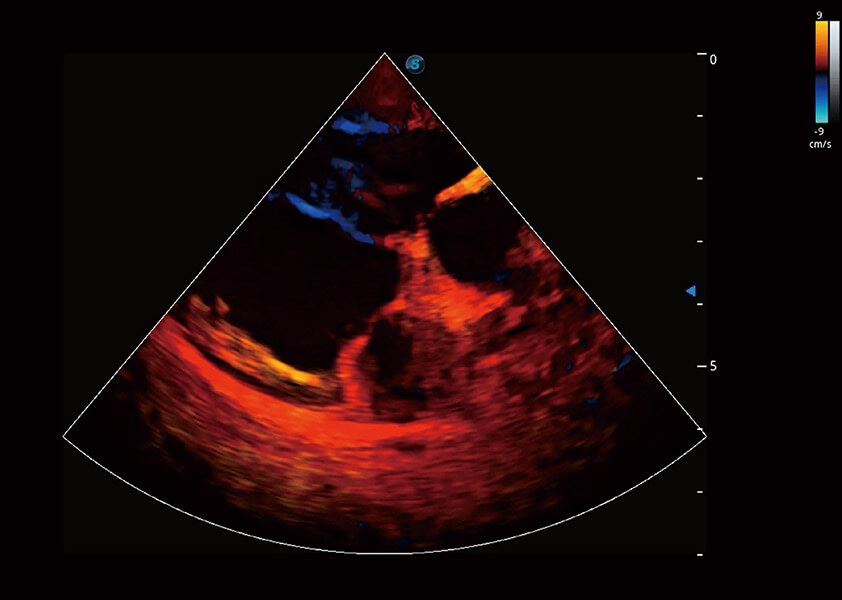

ProPet 60 作为一款高端台式动物超声设备,为动物医生的日常诊断提供了一系列贴合动物临床需求、解决临床实际问题的高级成像功能。凭借全系列高清探头,满足医生对腹部、心脏、生殖、浅表、肌骨等成像的所有需求,切实帮助您提升检查效率,提高诊断信心。

动物是人类最亲密的朋友和最值得信赖的伙伴。1xBET也一直致力于探索动物专用的超声影像解决方案。 全新推出的ProPet系列,是1xBET在动物超声影像智能化、专业化、精准化的一次跨越式革新。动物不能用言语来表述自己的不适,通过超声影像,ProPet系列搭建了动物医生与不同物种沟通的“桥梁”,为动物医生注入了“治愈之力”。